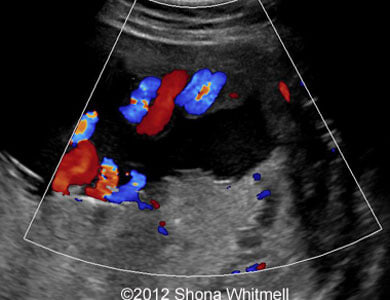

Figure 3, 4: 2-vessel umbilical cord on the placental end.

Image-16

Image-19